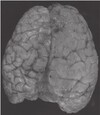

68

This patient had profound mental retardation, what is the diagnosis? A. Pachygyria B. Agenesis of the corpus callosum C. Polymicrogyria D. Agyria

**A. Pachygyria** B. Agenesis of the corpus callosum C. Polymicrogyria D. Agyria ## Footnote This brain demonstrates pachygyria, a form of lissencephaly, or neuronal migration disorders. The gyri are enlarged and fewer in number than normal brain. Further Reading: Psaaros. The Definitive Neurosurgical Board Review, page 110.